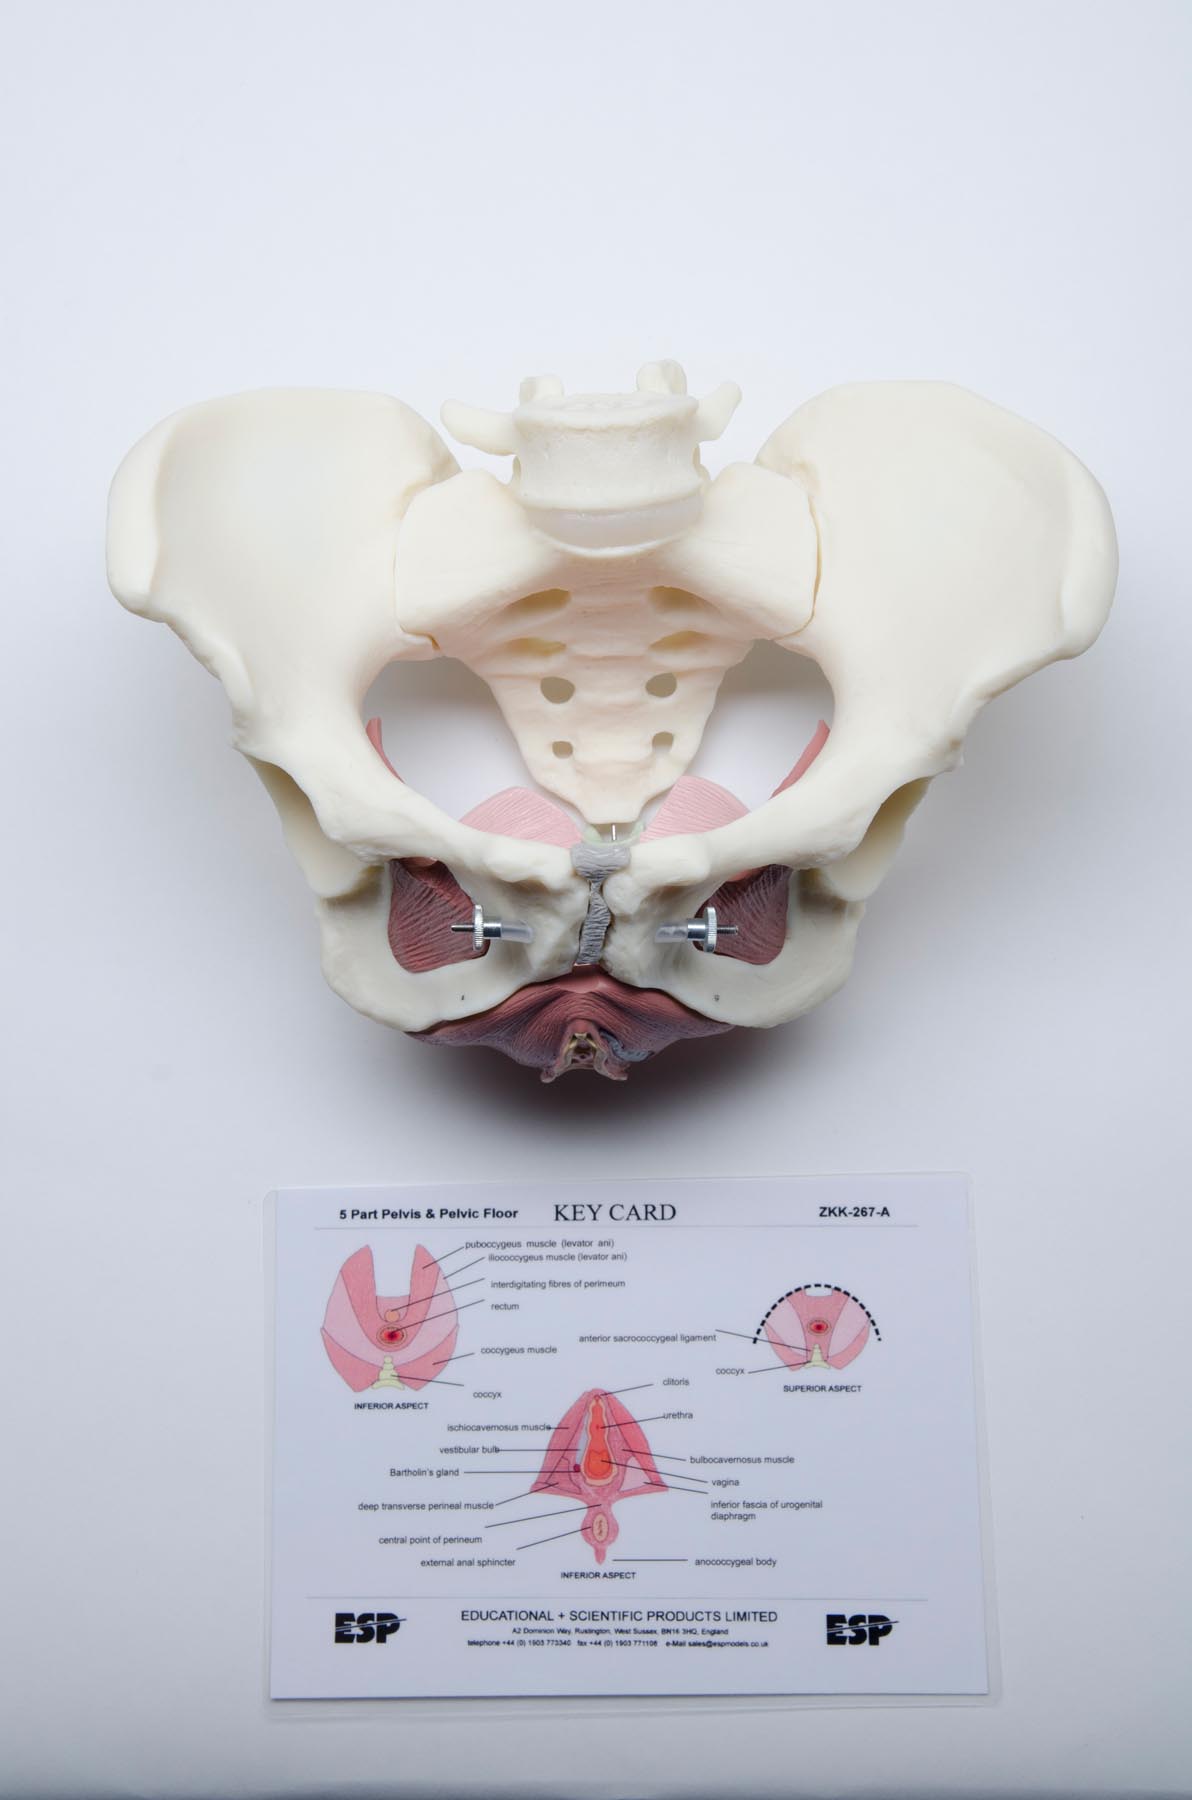

Female Pelvic Floor Educational Model

Female Pelvic Floor Educational Model

SKU: ESP-267A$629.28

A complete life-size female pelvis with a highly detailed pelvic floor made of flexible plastic. Features the genitalia and associated muscles. Dissects into 5 parts.

| Weight | 2.5 lbs |

| Dimensions | 11 × 8.5 × 8.25 in |